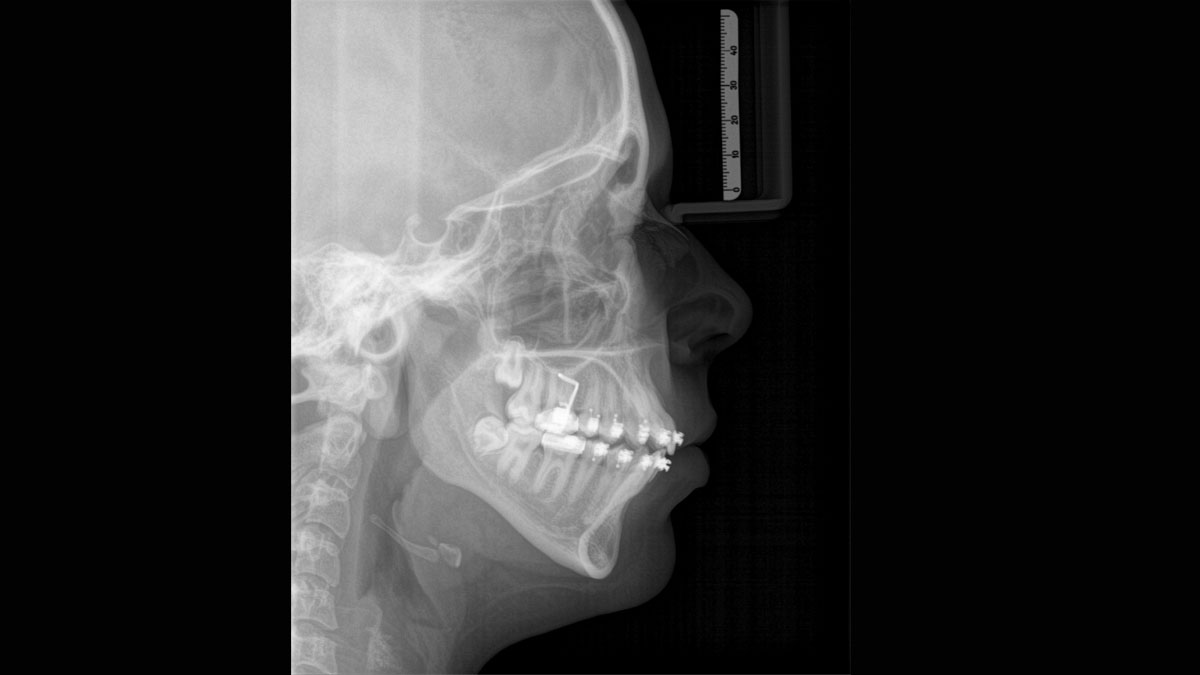

El equipo de radiología 2D/3D de alta calidad con una amplia gama de servicios para cada clínica. Ya sea como un dispositivo puramente 2D o como un módulo 3D, el Orthophos S es un socio confiable y está optimizado para las tareas diarias. Su sensor CsI Plus con función de autofoco garantiza imágenes claras, incluso en casos anatómicamente difíciles. El posicionamiento automático del paciente junto con el bloque de mordida oclusal patentado permite un posicionamiento del paciente fácil y que ahorra tiempo. Para su uso en ortodoncia, la Orthophos S también está disponible con un brazo cefalométrico opcional. Y como para Dentsply Sirona es importante estar preparado para el futuro, el brazo cefalométrico se puede reacondicionar en cualquier momento.

El brazo cefalométrico puede añadirse en el lado derecho o izquierdo de la unidad y solicitarse en el momento de la compra o instalarse en cualquier momento